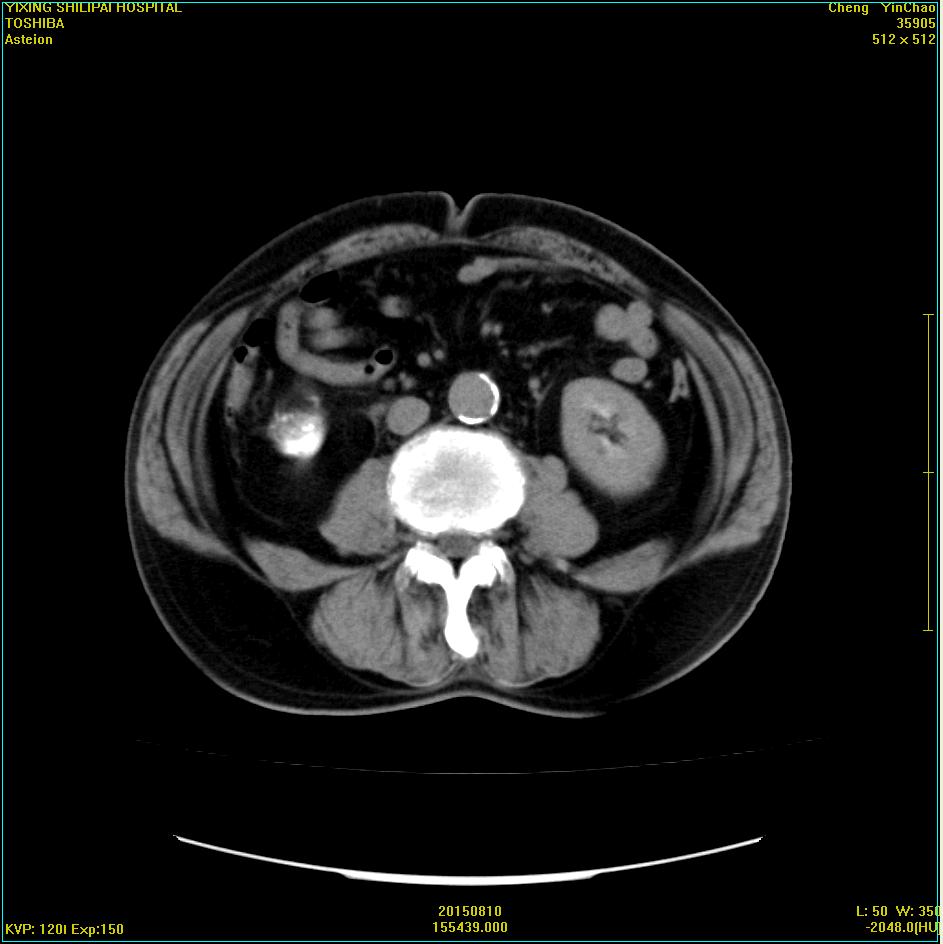

CT51011:会诊:右下腹肿块

本帖最后由 cefcmj 于 2015-8-16 22:10 编辑 男,77岁,右下腹痛半年余入院。30年前在新疆有阑尾手术切除史。 请问要考虑哪些疾病?目前还没有手术。

右下腹可见类圆形低密度占位,边缘钙化,与肠管粘连,

右下腹脓肿机化并钙化,结肠占位病变

结肠占位?建议行结肠镜检查。

病灶来源于阑尾,周围有钙化,考虑阑尾粘液性囊腺瘤。

慢性脓肿。致因:纱布瘤?